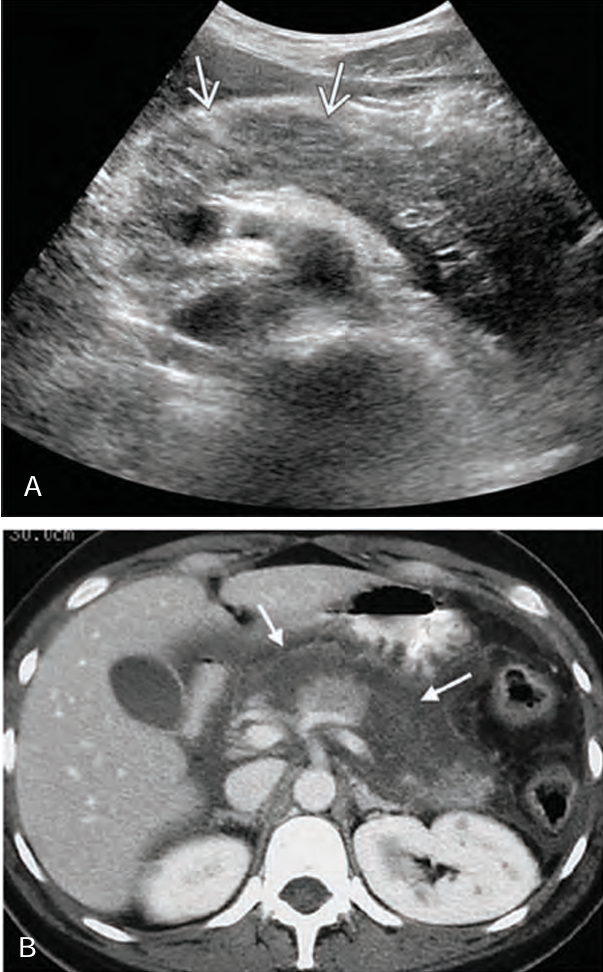

In the early stages of _____ pancreatitis, the sonographic appearance of the gland may _____ show _______ on sonography.

acute; NOT; swelling

When swelling does occur in acute pancreatitis, the sonographic appearance of the gland becomes ______ to _____ and is less _____ than the ______

hypoechoic; anechoic; echogenic; liver

When _____ does occur in _____ pancreatitis, the sonographic appearance of the gland becomes hypoechoic to anechoic and is less echogenic than the liver

Swelling; acute

_____ pancreatitis will have somewhat ______ but ________ borders, sonographically.

Acute; indistinct; smooth

Acute pancreatitis will have somewhat indistinct but smooth ______, sonographically

Borders

Sonographically, hemorrhagic pancreatitis depends on the ____ of the hemorrhage

age

Sonographically, a ______ necrosis may be seen as a ___- defined, ________ mass in the area of the pancreas

fresh; well; homogenous

Sonographically, at ____ week, the mass (hemorrhage) may appear ____ with ____ elements or _______

1; cystic; solid; septation

Sonographically, after _____ weeks, the hemorrhage may appear ______

several; cystic